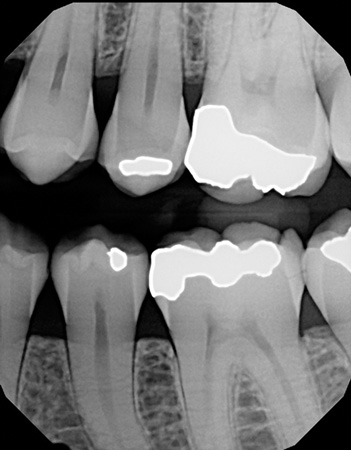

Figure 1: Cracked tooth x-ray

I used it on an elusive cracked tooth case. For once, I could actually see the fracture on an x-ray (figure 1). The noted distal fracture caused a great deal of biting pain for this patient. The one difference I noticed with All-Bond is its application method. Two coats are required and a scrubbing motion is needed during the two-coat process prior to curing. Yes, this is a little more time-consuming, but it did not bother me as much as I thought it might when I initially read the application directions. After I saw the results on the x-ray (figure 2), I knew the thin viscosity did not prohibit any type of condensed end product. The composite material flowed well into the proximal areas, and my patient left with no cracks in No. 19.

Figure 2: Restored cracked tooth x-ray